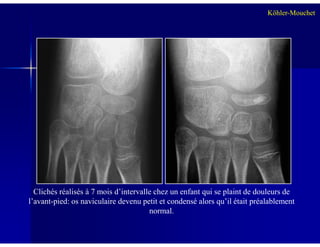

Clichés réalisés à 7 mois d’intervalle chez un enfant qui se plaint de douleurs de

l’avant-pied: os naviculaire devenu petit et condensé alors qu’il était préalablement

normal.

Radiographie:Radiographie:

Ostéocondensation hétérogène de l’osOstéocondensation hétérogène de l’os

naviculaire, fragmentation et diminution de lanaviculaire, fragmentation et diminution de la

taille (aplatissement antérotaille (aplatissement antéro--postérieur),postérieur),

tuméfaction des parties mollestuméfaction des parties molles

Attention aux variantes anatomiques !!Attention aux variantes anatomiques !!

3 critères pour retenir le diagnostic:3 critères pour retenir le diagnostic:

-- Signes cliniques au moment du diagnostic +++Signes cliniques au moment du diagnostic +++

-- Modifications d’un os naviculaire précédemmentModifications d’un os naviculaire précédemment

normal sur les RXnormal sur les RX

Maladie de Köhler-Mouchet

-- Résorption osseuse et réRésorption osseuse et ré--ossification en rapportossification en rapport

avec une ostéonécroseavec une ostéonécrose